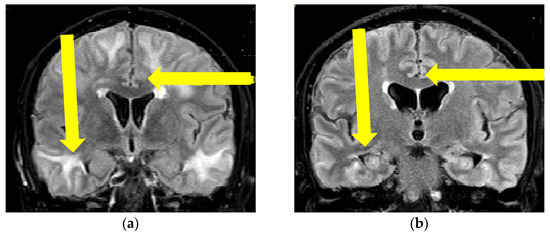

Figure 2.

Initial brain MR T2 FLAIR sequence (a), and control brain MR examination after immunosuppressive therapy initiation (b). Yellow arrows showing the locations of hyperintensities and clear regression of lesions (Patient No. 1).

Since the patient fulfilled all the criteria for the diagnosis of probable CAA-ri (age > 40 years, decreased consciousness, with the presence of behavioral changes and focal neurologic deficit, MR signs of asymmetric WMH lesions and cerebral microbleeds, with the absence of other possible causes), the patient was initially treated with antihypertensive and anti-edematous therapy, together with IV dexamethasone (8 mg/daily) for 10 days, followed by pulse methylprednisolone therapy (1000 mg/day) for 5 days, after which oral prednisone (1 mg/kg) was slowly tapered down. The patient’s neurological status improved and he showed very discrete hemiparesis and normal gait, and the patient was alert and oriented. A neurological examination was almost without significant impairment and sequelae. A control CSF examination was performed, where normal levels of protein and glycose were detected. A normal cell count was present, and no OCB were registered. Control brain MR showed edema reduction with less extended WMH lesions (Figure 1 and Figure 2). The post treatment neuropsychological examination was without significant impairment.